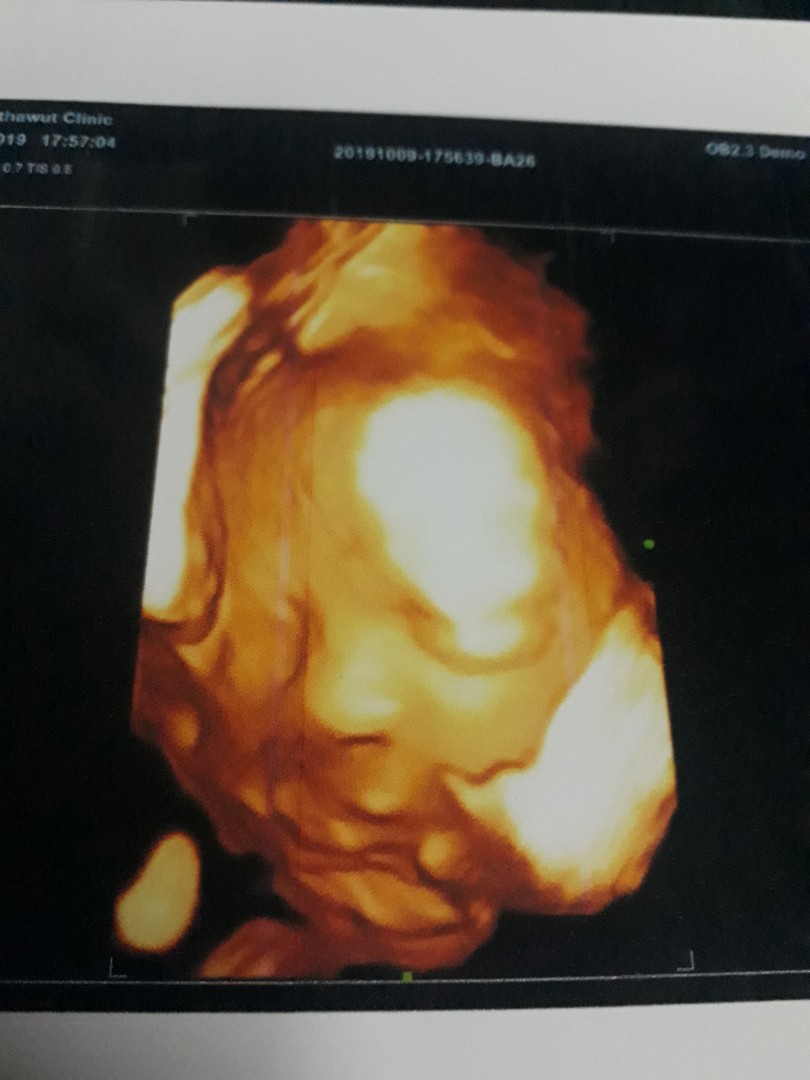

เอาเด็กชายปากคว่ำ เดือน พย. มาอวดจ้า

อายุครรถ์ 32วีค5วัน ผมหนัก 2,100 แล้วครับ ขอดูเด็กเดือน พย. น่ารักๆหน่อยครับ ผมไม่ชอบเลยเวลาคุณหมอซาวด์ หน้าจะบึ้งหน่อยๆ55555

ซาวที่ไหนได้บ้างคะ ชัดขนาดนี้

อ่อค่ะ ชัดมากค่ะ แถวบ้านไม่ชัดแบบนี้เลย

เสีย1,000 พร้อมยาบำรุงคะแม่ รูปเอามือถือถ่ายเอา กลัวปริ้นแล้วแพง